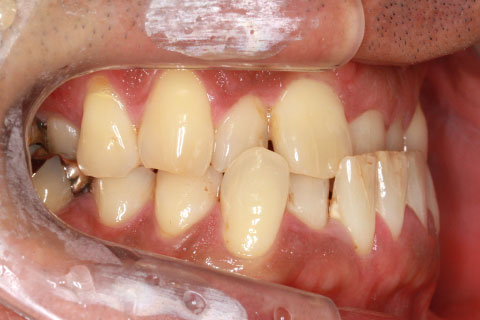

フルリンガル矯正2:上下の歯を舌側矯正で治療(矯正期間18ヶ月)

- 年齢・性別

- 42歳男性

- 治療期間

- 1年6ヶ月

- 抜歯

- なし

- 治療費

- 120万円(税込み)

- 備考

- マルチブラケットを用いた矯正治療

- 治療内容

- 反対咬合をフルリンガル矯正治療にて改善

- 施術の副作用(リスク)

- 表側矯正と比較して、歯根の角度を確立する「トルク」の力がかかりにくい。